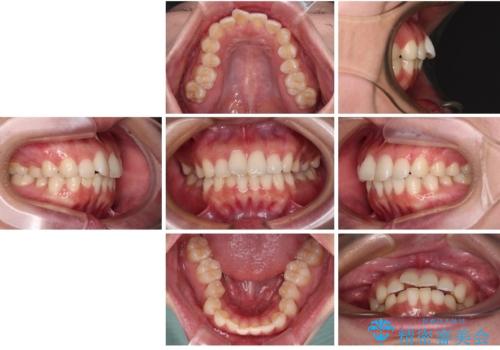

- 全体的なデコボコと口元の突出感を改善したいとのことで来院された患者様です。

このままデコボコを整えるとさらに突出感が増すため、上下左右の第一小臼歯を抜歯し、ワイヤー装置にて矯正しました。

結婚式で途中装置を外した時期がありましたが、2年で治療を終えることができました。